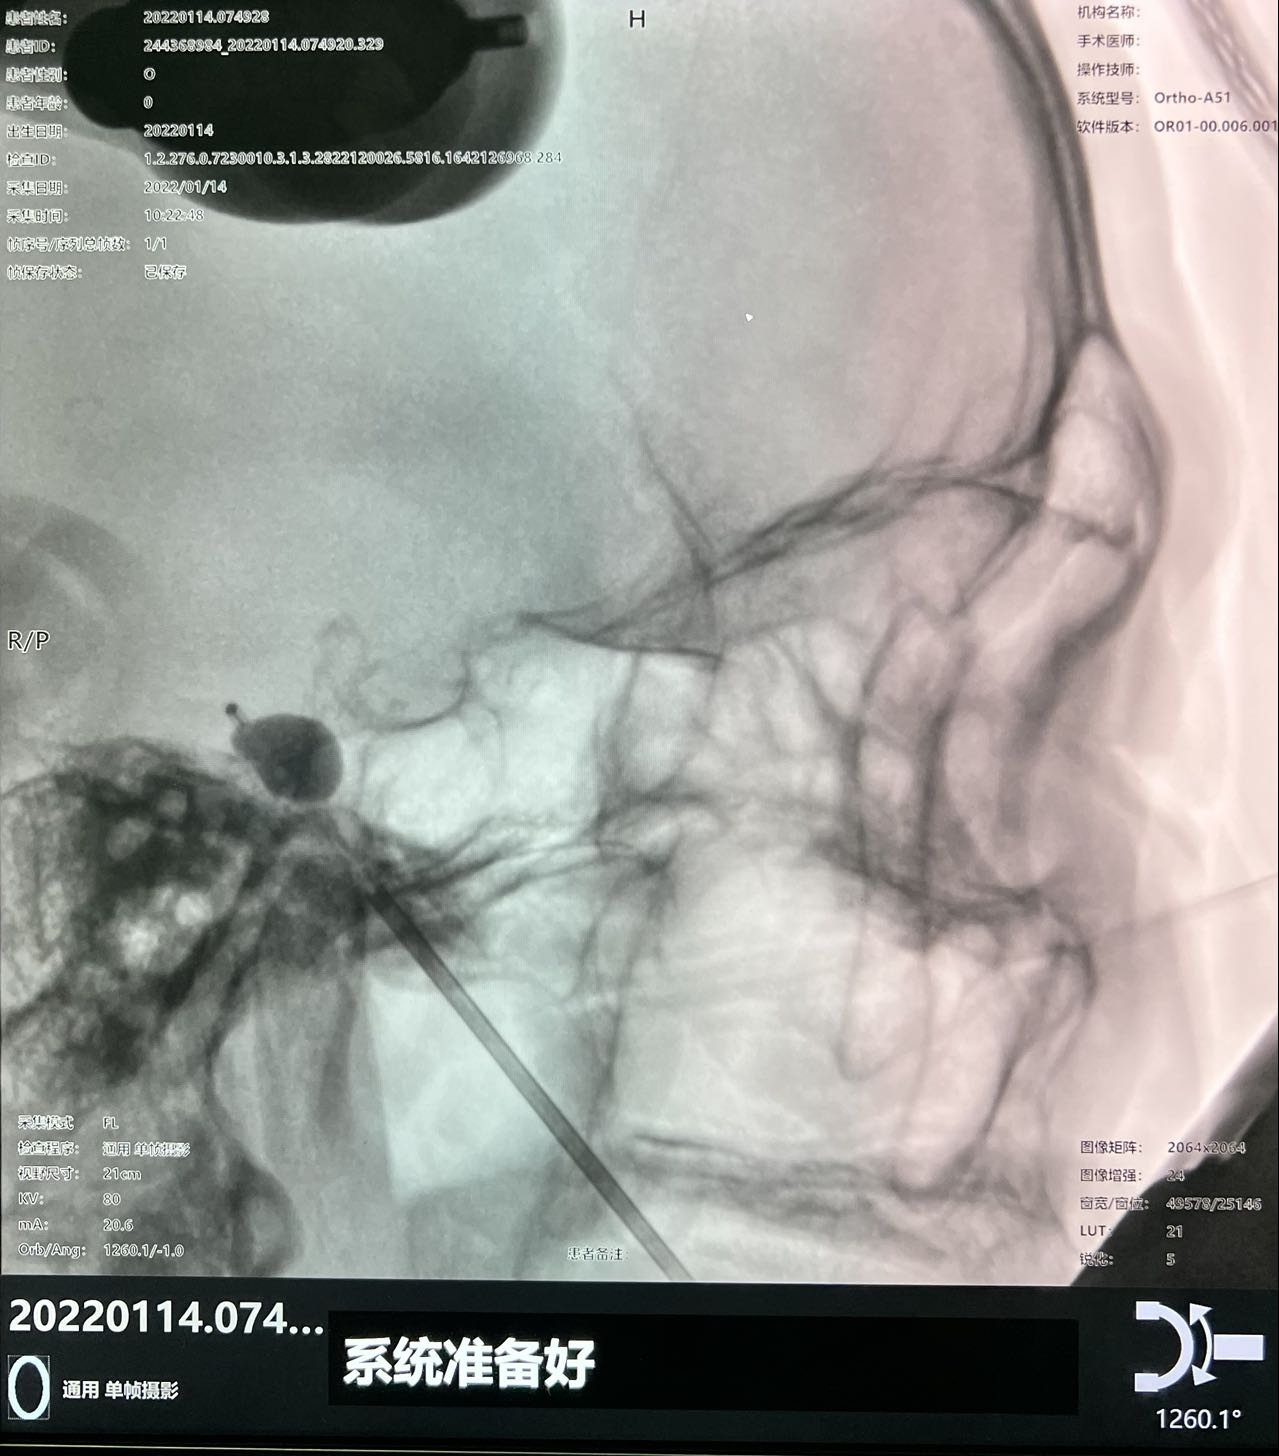

图4 术中C型臂透视显示:球囊成形好,压迫满意

但该患者手术需要精确的三维定位,术中需把穿刺针准确穿入皮下约8cm深、直径仅为3mm左右的卵圆孔,传统方法只能在C型臂引导下徒手穿刺,一次性穿刺成功率低。如何高效率穿刺成功,从而减少患者术中风险成为了迟令懿团队亟待解决的问题。在神经外科副主任李卫国的指导下,迟令懿采用机器人辅助立体定向下穿刺。术前验证误差仅为0.3mm,术中仅用10秒钟即完成了穿刺操作,避免了反复穿刺导致的血管、组织损伤,减少了C型臂透视的次数,降低了手术风险和并发症。术后,患者面部疼痛即刻消失,1天后顺利出院。